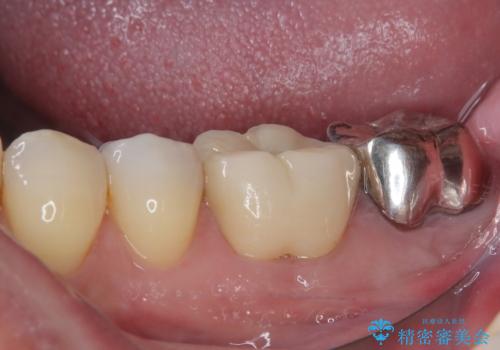

- 奥の銀歯が外れしまったとのことで来院された患者様です。

非常に咬合力が強く、銀歯の周りの歯がむし歯になっている状態でした。

部分的な詰め物ですと、再度周辺がむし歯になるリスクが高いと考えられたため、オールセラミッククラウンにて補綴治療を行うこととしました。

ゴールドのような金属の詰め物は、削る範囲を最小限にし、厚みもセラミックと比べて薄くできるため、セラミックのようにクラウンにせずに治療を行うこともできますが、保険診療である銀歯では、どうしても適合が悪く隙間ができてしまうので、今回のような周辺がむし歯になる可能性が高くなってしまいます。